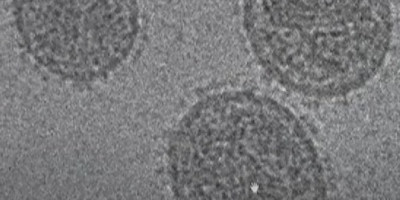

Oksfordski naučnici objavili su otkriće visoko virulentne varijante HIV-a koja se decenijama skrivala u Holandiji

Oni, međutim, ističu da zbog efikasnosti savremenih načina lečenja, nema razloga za zabrinutost. Njihova analiza, objavljena u časopisu „Sajens“, pokazala je da su pacijenti zaraženi „VB varijantom“ imali u krvi 3,5 do 5,5 puta viši nivo virusa od osoba zaraženih drugim varijantama. Kod njih je zabeleženo i brzo slabljenje imunog sistema.

Studija je pokazala da su, nakon početka lečenja, osobe sa varijantom „VB“ imale sličan oporavak imunog sistema i preživljavanje kao osobe sa drugim varijantama HIV-a. Vodeći autor studije, epidemiolog Kris Vajmant je za AFP izjavio da bi otkriće varijante HIV-a trebalo da bude „upozorenje da nikada ne bismo smeli da budemo previše samouvereni u vezi sa tvrdnjom da će virusi evoluirati samo da bi postali blaži“. Tim je ukupno pronašao 109 osoba zaraženih varijantom „VB“, od kojih samo četiri žive van Holandije, ali u zapadnoj Evropi.

Virus mutira

Virus HIV-a se stalno razvija, u toj meri da svaka zaražena osoba ima malo drugačiju verziju. „VB“ varijanta ima preko 500 mutacija. „Pronalaženje nove varijante je normalno, ali pronalaženje nove varijante sa neuobičajenim svojstvima nije, posebno one sa povećanom virulentnošću“, objasnio je Vajmant. Naučnici su prvo identifikovali varijantu „VB“ kod 17 HIV pozitivnih osoba analizirajući podatke iz projekta „BEEHIVE“, inicijative za prikupljanje podataka i analizu u Evropi i Ugandi. S obzirom da je 15 bilo iz Holandije, proučili su podatke 6.700 HIV pozitivnih Holanđana i potvrdili još 92 slučaja.

Prvo pojavljivanje varijante „VB“ pronađeno je kod osobe kojoj je zaraza dijagnostikovana 1992. godine, dok je najstarije otkriće kod osobe zaražene 2014. Varijanta se najverovatnije pojavila krajem 1980-ih i početkom 1990-ih u Holandiji, ali je počela da se povlači oko 2010. Kako ističu, otkrivanje zaraze u ranoj fazi i lečenje su presudni, preneo je portal „Indeks“.